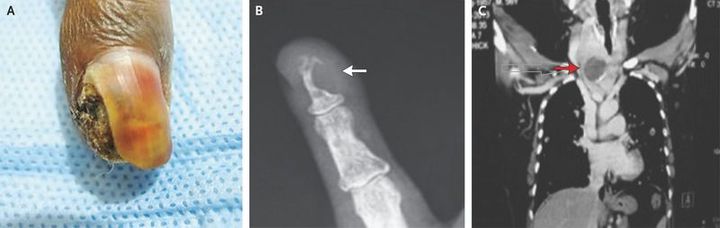

A 50-year-old woman presented with a painless lesion deep in the nail of the left little finger, which she had first noted 2 months earlier. There was no history of associated trauma or pruritus. The physical examination revealed a firm 2-cm lesion with a scab in the center (Panel A). The overlying nail was dystrophic and partially separated from the nail bed. Finger movements were normal. Radiography of the left fifth digit revealed a lytic lesion involving the terminal phalanx (Panel B, arrow). There was also diffuse enlargement of the thyroid gland, with a dominant nodule at the isthmus. Computed tomography of the chest showed an enlarged thyroid with retrosternal extension and a dominant nodule (Panel C, arrow), as well as multiple pulmonary nodules. Fine-needle aspiration of the thyroid nodule revealed a follicular neoplasm, and biopsy of the phalangeal lesion revealed metastasis from follicular thyroid carcinoma. The patient underwent total thyroidectomy. During radioiodine scanning, uptake was noted in the left little finger as well as in the choroid of the eye, thereby highlighting the iodophilic nature of these metastases. After radioiodine therapy, there was complete regression of the digital metastasis.